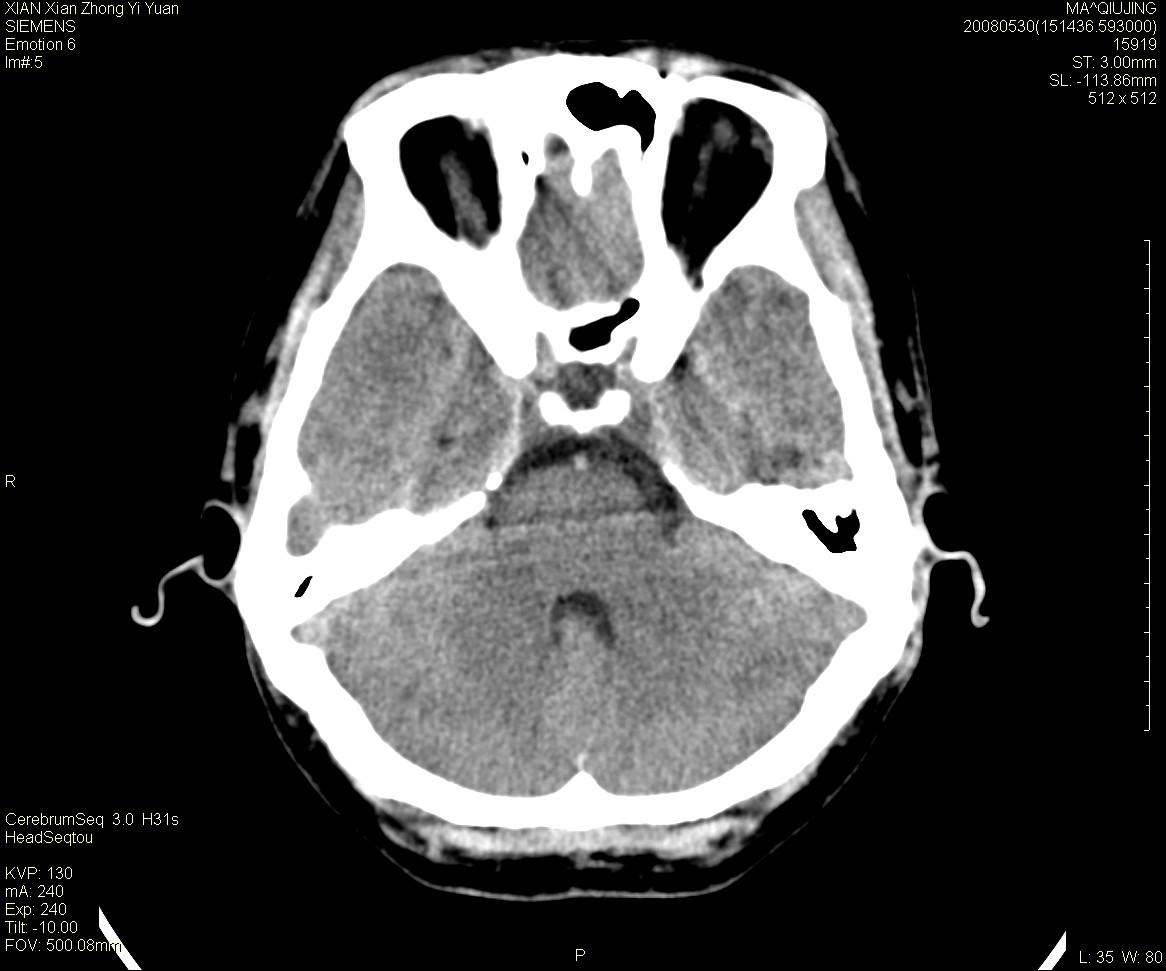

标题: CT13768:少见病例,血管畸形。

患者m47,头晕数年,没给强化,让做dsa去了。

avm

第一感觉:avm,但其中更低密度区不清楚,好像有脂肪密度,胆脂瘤破裂?

avm,低密度区应该是以前出血过的液化灶

血管畸形,支持,如果增强扫描,则可见粗大,迂曲血管团。